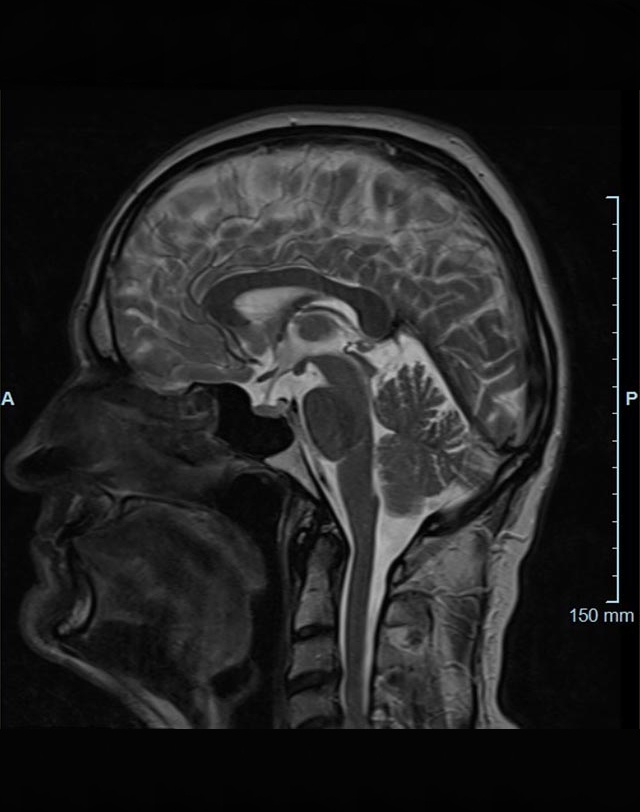

Kopf/Hals

• akute Schlaganfalldiagnostik und chronische Durchblutungsstörungen

• entzündliche Prozesse des Gehirns oder der Gesichtsweichteile

• Tumore

• Abklärung Schwindel, zentrale Sehstörung, Kopfschmerz

• Metastasenverdacht

• Multiple Sklerose

• Abklärung Hirnnerven, Schädelbasis inkl. Hypophyse

• Abklärung Kleinhirn, Hirnstamm, Halsmark

• intrakranielle Gefäße (Abklärung Verschluss, Stenose, Aneurysma)